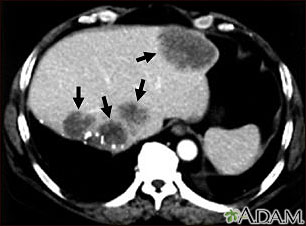

TC de la parte superior del abdomen de un paciente con carcinoma del intestino grueso que muestra metástasis múltiple hacia el hígado. Observar las áreas oscuras en el hígado (lado izquierdo y al centro de la imagen).